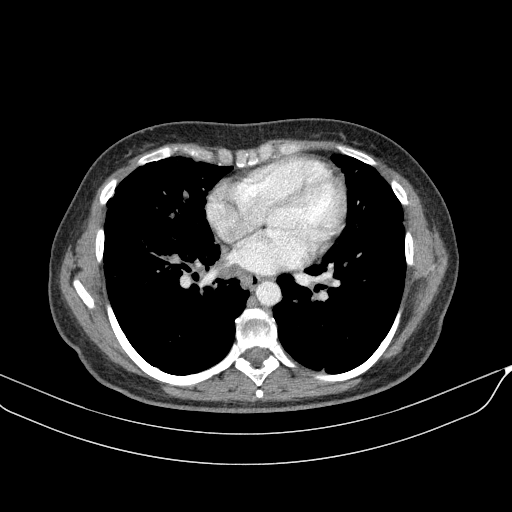

Image Grid

4Γ—3 grid: Rows show different image types (Original NATIVE, Reconstructed NATIVE, Original VENOUS, Generated VENOUS), Columns show windowing techniques (No Window, Lung Window, Mediastinum Window)

Mediastinum window (WL 40, WW 400 β†’ Low βˆ’160, High +240)

Original NATIVE CT scan (input)

Original VENOUS CT scan

Generated VENOUS CT scan (A→B translation)

Targeted Slice 70 - Mediastinum Window Analysis (Generated vs Real Venous)

0.709

Mediastinum SSIM

83.3

Mediastinum RMSE

34.9

Mediastinum MAE